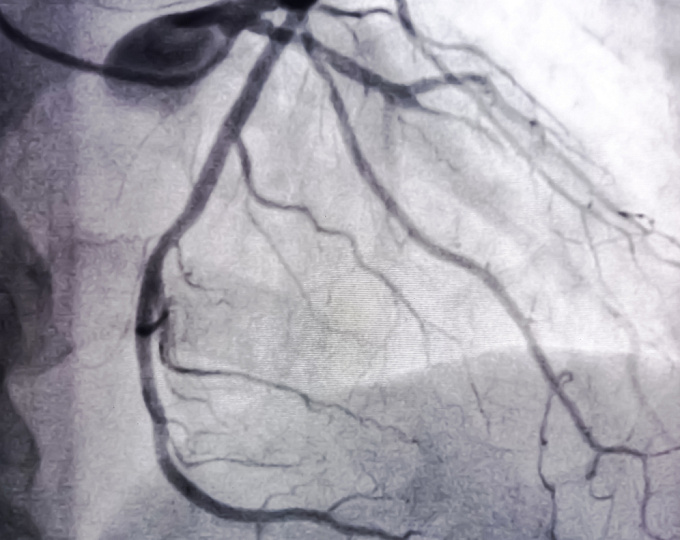

Ацетилсалициловая кислота в сочетании с внутривенным иммуноглобулином используются с целью профилактики развития повреждений коронарных артерий при болезни Кавасаки.

Первичной конечной точкой было поражение коронарных артерий в течение 6 недель.

В исследовании приняли участие 134 пациента (средний возраст 1.8 г.; 61% мальчики). В группе сочетанной терапии внутривенным иммуноглобулином и аспирином частота выявления поражений коронарных артерий уменьшилась с 13% на момент начала исследования до 2.9% на момент его окончания. Аналогичные значения в группе монотерапии внутривенным иммуноглобулином составили 11 и 1.5%, соответственно (p=0.65).

Таким образом, у детей с болезнью Кавасаки монотерапия внутривенным иммуноглобулином была не хуже терапии внутривенным иммуноглобулином и аспирином с точки зрения выраженности поражений коронарных артерий.